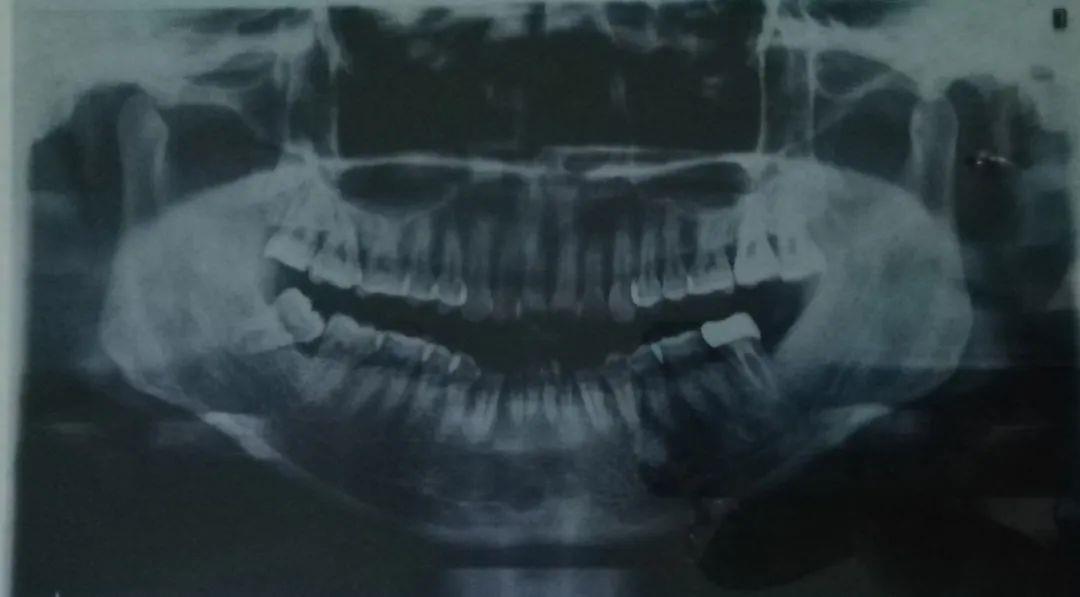

比如ct片、牙片,可以清晰的看出牙齿的问题

我拍出的片子……真是一言难尽

我不惜献丑让大家看我的牙片,正面看主要是中间牙齿的排列不齐,但从侧面看简直惊人,以前觉得我的凸嘴可能就是骨性问题,也不觉得上牙齿有多难看,看牙片就会发现这龅牙龅的也太离谱,不整都对不起自己。